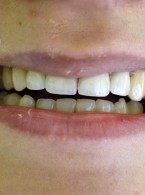

Pokrycie mnogich recesji dziąsłowych

metodą płata przesuniętego dokoronowo z wykorzystaniem przeszczepu podnabłonkowej tkanki łącznej i kolagenowego materiału ksenogennego po wcześniejszej rekonstrukcji połączenia szkliwno-cementowego - opis przypadku